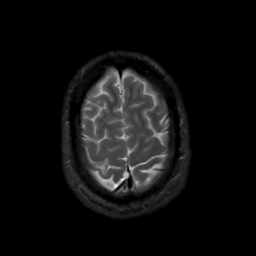

MR Study #8, March 31, 1991 -- Slice #43

[Home][Help][Clinical][Tour 1][Tour 2] Slice 43